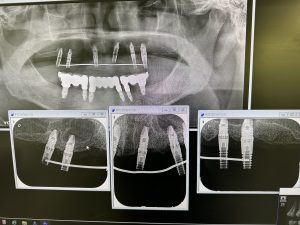

今日はインプラント仮歯セット

8年前に可撤性のケラター義歯を装着し問題なく経過しているが、患者さんの希望で固定性へ変更

今では使わない、プラットフォームマッチングTYPEだが、8年経過しているが骨吸収は無し

HAコーティングのバイオインテグレーションtypeだから結合力が非常に強い、オスオインテグレーションよりも強固!

現在でも密着値ISQは80台半ば!

今後は粘膜面の形態を整え、噛み合わせがなじみ、発音等良くなり次第、完成に移行

以前よりもマメにブラッシングに、更に噛み合わせ与え方は、緩やかなグループファンクションが肝です!